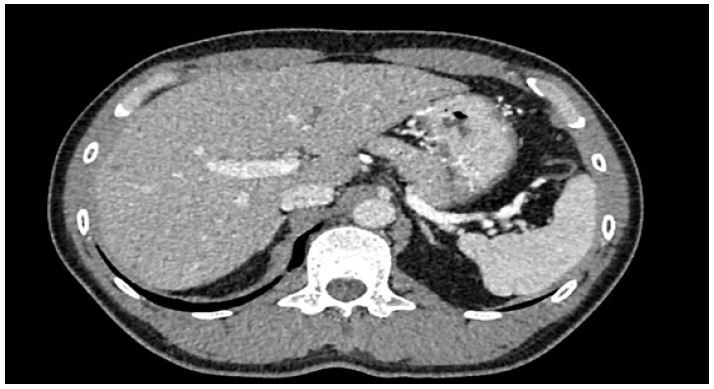

This patient was treated by medication; bronchodilator inhalator for symptomatic relief, molnupiravia (200 mg) 1 tab every 12 hours for 5 days. He was still complaining of fatigue and dyspnea. After failure of medication treatment, the electrocardiography and echocardiography were requested for re-evaluation. The result of that investigation showed normal. The CT chest was performed and reported innumerable Too Small to Characterize (TSTC) lesion scattering both hepatic lobes (Figure 1). The further Magnetic Resonance Imaging (MRI) revealed innumerable cystic lesion in both lobes of liver, (Figure 2). TW showed a signal lower than the liver parenchyma and T2W showed cystic hyperintensity like a ‘starry sky’ (Figure 3).

Figure 2: Non-enhancement liver cystic lesion; (A) Pre-gadolinium, (B) Arterial phase, (C) Venous phase, (D) Delay post-gadolinium.

VMCs usually do not cause symptoms and incidental finding with recent noninvasive imaging modalities. Most of biliary hamartoma are composed of small, 5-30 mm disorganized clusters of dilated cystic bile ducts that appear throughout the liver and generally do not communicate with biliary tree [8]. The CT scan of VMCs consists of multiple small, low attenuated areas that do not enhance on contrast injection. MRI of liver and MRCP show low signal intensity on T1-weighed and high signal intensity on T2-weighed images sequences give the liver a ‘starry sky’ appearance [9-11].